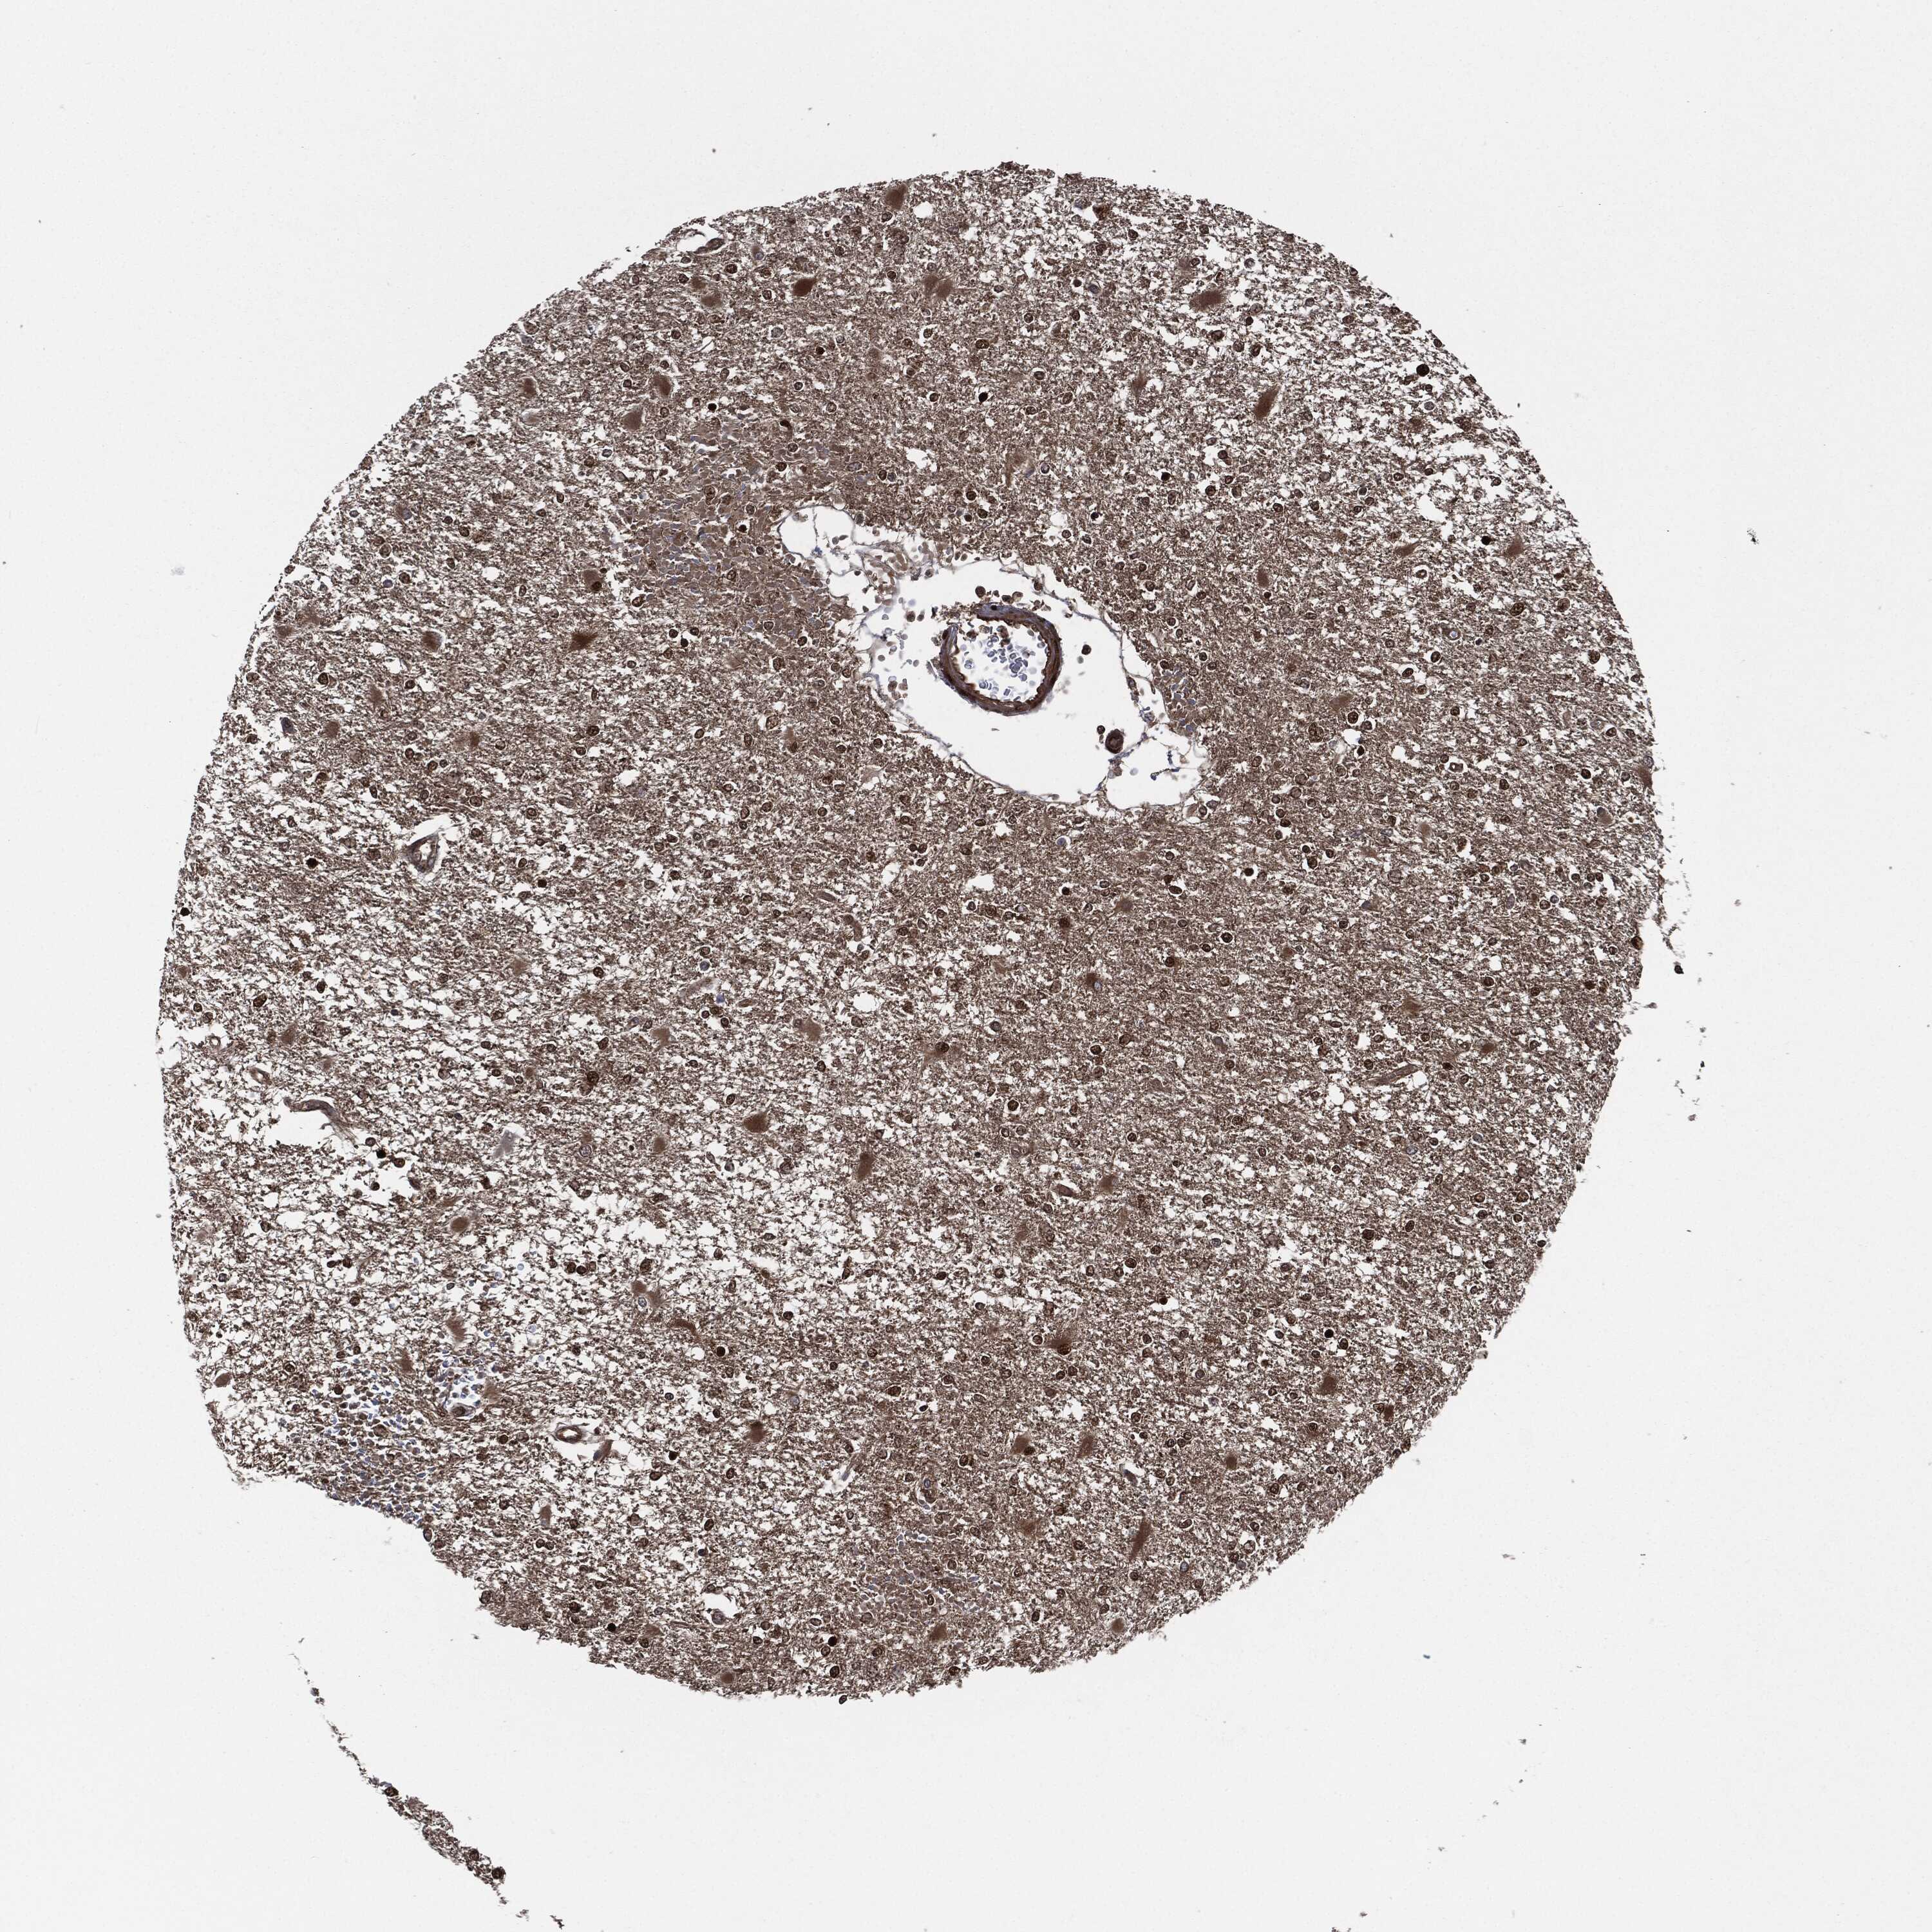

GLIOMA - Protein expressioni

A mouse-over function shows sample information and annotation data. Click on an image to view it in a full screen mode. Samples can be filtered based on level of antibody staining by selecting one or several of the following categories: high, medium, low and not detected. The assay and annotation is described here.

Note that samples used for immunohistochemistry by the Human Protein Atlas do not correspond to samples in the TCGA dataset.

Antibody stainingi

Antibody staining in the annotated cell types in the current human tissue is reported as not detected, low, medium, or high, based on conventional immunohistochemistry profiling in selected tissues. This score is based on the combination of the staining intensity and fraction of stained cells.

Each image is clickable and will lead to virtual microscopy that enables deeper exploration of all samples and also displays staining intensity scores, fraction scores and subcellular localization as well as patient and tissue information for each sample.

Antibody HPA034635

Antibody HPA069977

Antibody HPA071875

Antibody CAB009108

Staining

High

Medium

Low

Not detected

Intensity

Strong

Moderate

Weak

Negative

Quantity

>75%

75%-25%

<25%

None

Location

Nuclear

Cytoplasmic/membranous

Cytoplasmic/membranous,nuclear

Glioma, malignant, Low grade

Glioma, malignant, High grade